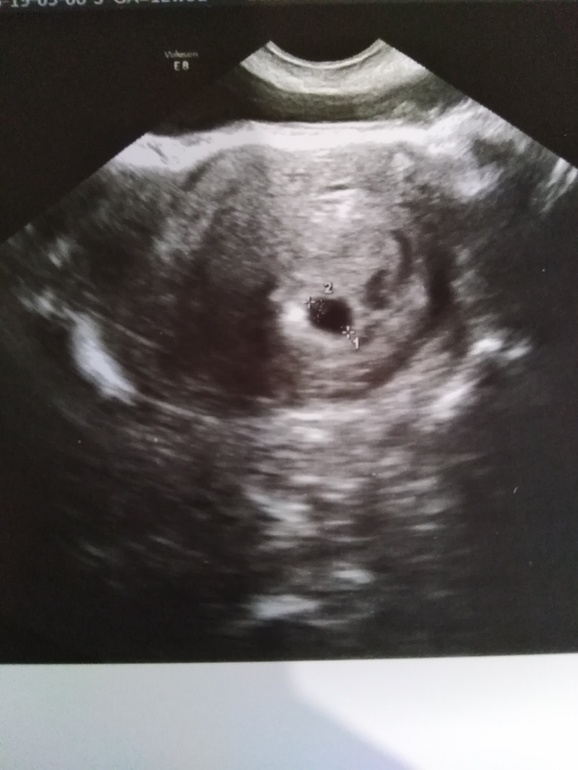

Всё о нашей беременностиПривет мои ББ😊, сегодня 19дпп, сходили мы сегодня на узи, познакомились с нашем сокровищем, божечки какой он маленький, но такой любимый, наше маленькое счастье. Не забываемые эмоции которые не возможно передать словами. Каждай из вас я желаю такого же счастья, пускай у каждой из вас будет такое фото и такая прекрасная книжка😍😍😍😘😘😘

Ещё нет, через 10 дней пойдём сердечко слушать и эмбриошку смотреть, может и второго увидем, очень на это надеюсь. Спасибо большое.